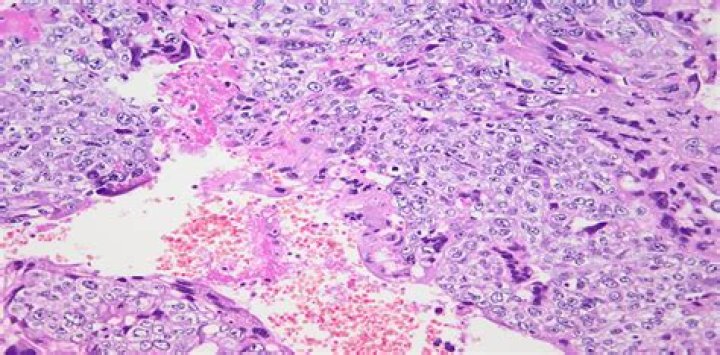

Choriocarcinoma is a malignant proliferation of trophoblasts that complicates a normal or abnormal pregnancy. Intraparenchymal brain metastases from choriocarcinoma occur in 10-20 % of the cases and are often haemorrhagic.

Unlike a hydatidiform mole, a choriocarcinoma is a malignant and more aggressive form of GTD that spreads into the muscle wall of the uterus. A choriocarcinoma can also spread more widely to other parts of the body such as the lungs, liver, and/or brain.

How can you tell the difference between choriocarcinoma and invasive mole?

Invasive mole is unlike choriocarcinoma, the latter is without the presence of chorionic villi. It is important to distinguish between invasive mole and choriocarcinoma, as the former has a more favorable outcome.